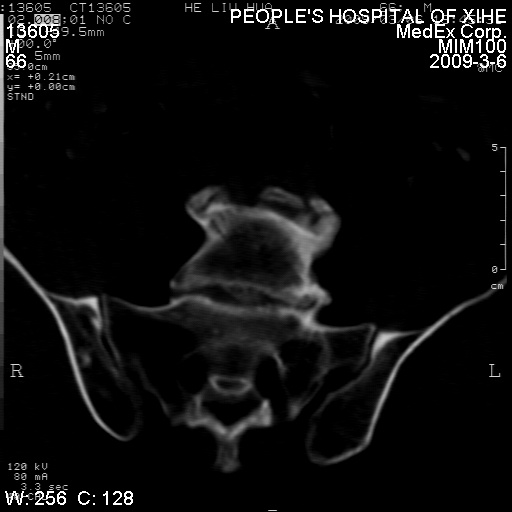

标题: CT18522:男,66岁。考虑结核有错吗 [打印本页]

标题: CT18522:男,66岁。考虑结核有错吗

x线片示:骶骨密度增高。

考虑----腰椎骶化-----退变-----椎管狭窄

退行性变,椎体滑脱

腰椎滑脱并有退变

退行性变,椎体滑脱。建议同椎体平行进一步扫描。